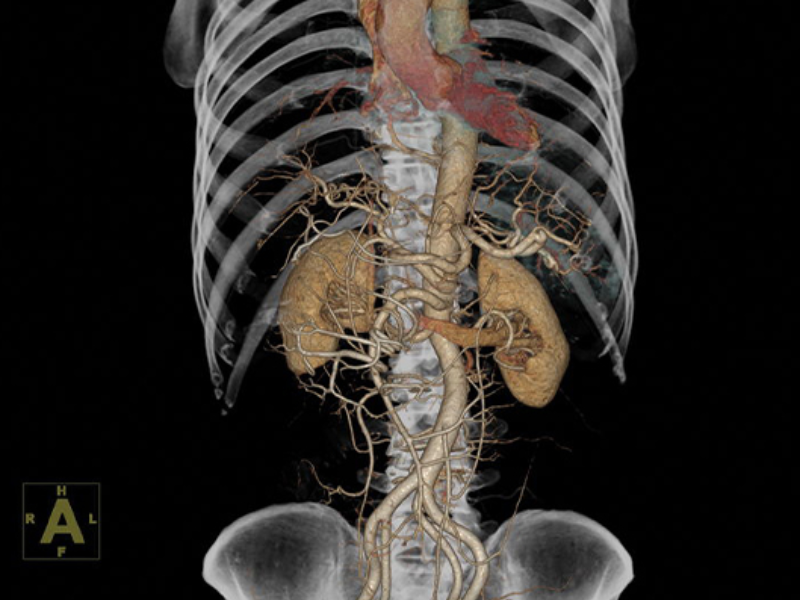

VRT of Abdomen

2 mm MIP